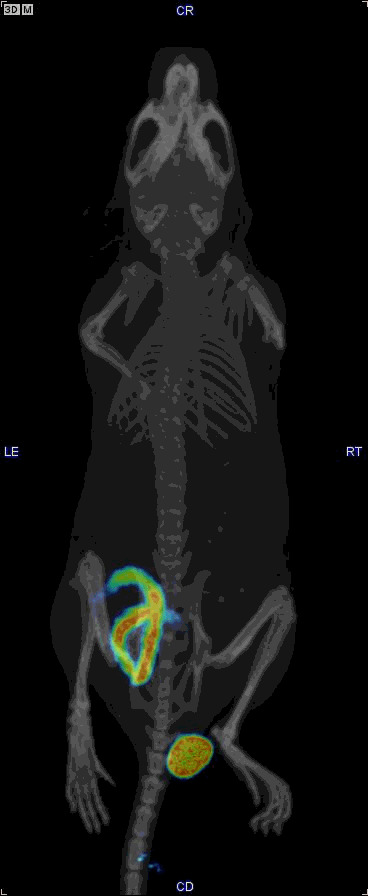

Gallery

This is a gallery of images and videos from various projects etc.